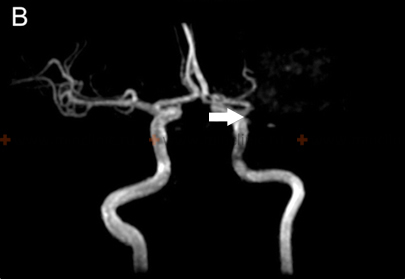

If cerebral artery embolism is suspected, identifying the location of the arterial occlusion and assessing the downstream brain tissue is critical for guiding acute treatment (like thrombectomy) [16, 19]. Non-invasive vascular imaging, such as CT angiography (CTA) or MR angiography (MRA), is typically performed urgently [16]. Conventional catheter-based cerebral angiography (Digital Subtraction Angiography - DSA) provides the highest resolution detail of the vessels but is invasive [14]. It may be performed if endovascular treatment (thrombectomy) is planned or if non-invasive imaging is inconclusive [16, 19]. It's important to note that after several hours or days, an embolus might migrate distally, fragment, or undergo spontaneous lysis (dissolution), meaning that angiography performed later might not show the original occlusion, making the definitive diagnosis of embolic stroke sometimes presumptive based on clinical presentation and infarct pattern [1]. Standard intravenous contrast administration during a routine CT or MRI scan generally lacks the resolution and timing necessary to directly visualize small cerebral emboli within vessels [14].